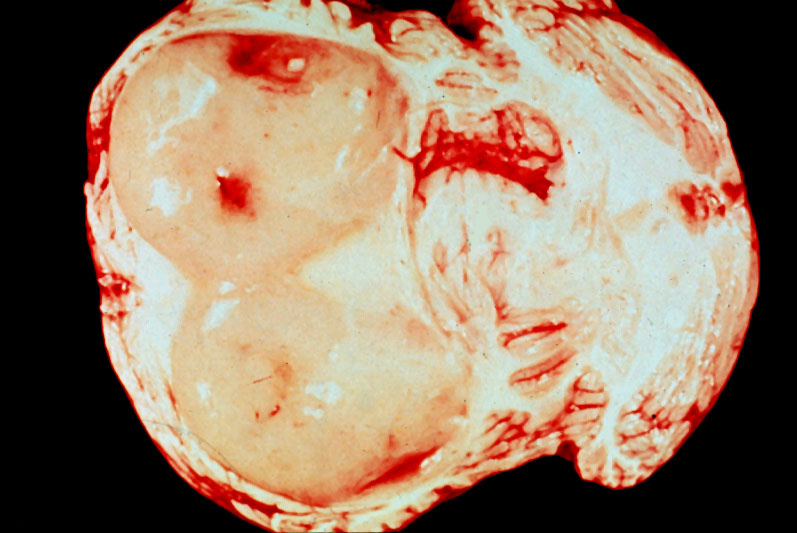

Brain, cerebellar astrocytoma, gross

Cystic cerebellar astrocytoma with mural nodule from a 6 year old girl. This is a benign neoplasm and totally curable by resection, even if only the mural nodule is excised. Unfortunately, this child was not operated on and died of increased intracranial pressure in the posterior fossa and herniation of the cerebellar tonsils..